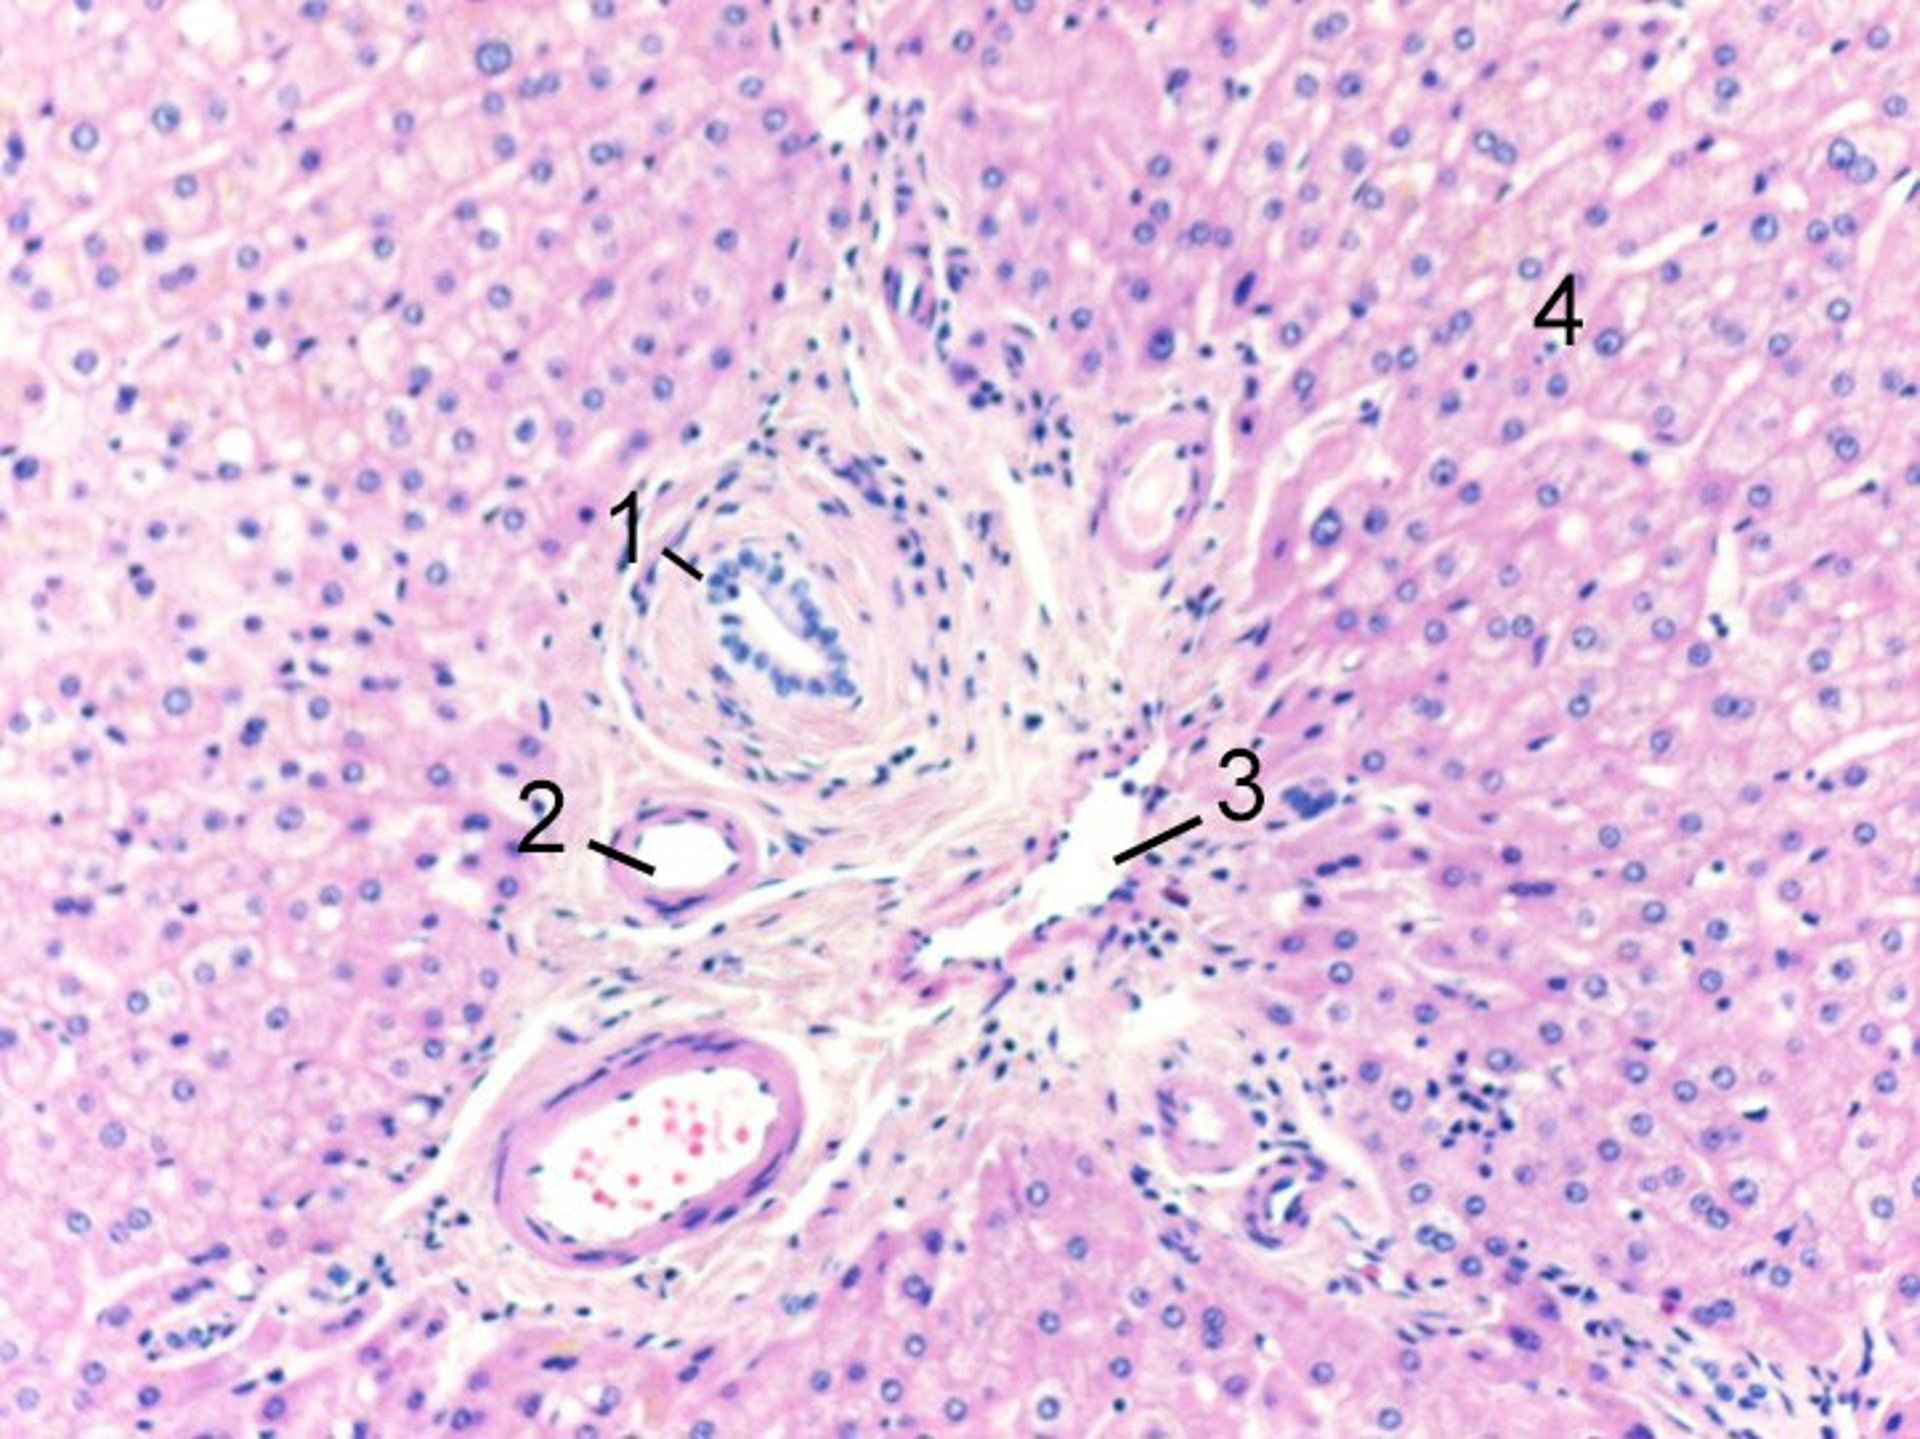

正常门管三联体

1=胆管分支;2=肝动脉分支;3=门静脉分支;4=肝细胞。

Image courtesy of Danielle Tholey, MD, and M.Isabel Fiel, MD, MS, FAASLD.